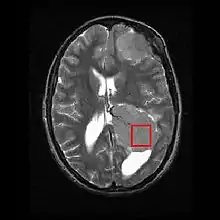

طیفنگاری با تشدید مغناطیسی (MR Spectroscopy) نام یک روش سنجش متابولیت بکمک تصویربرداری تشدید مغناطیسی است.

این تکنیک امروزه برای تصویرگیری از مغز کاربردهای فراوانی دارد. به ویژه از دنبالههای پالسی PRESS و STEAM در این روش استفاده میگردد.[1]